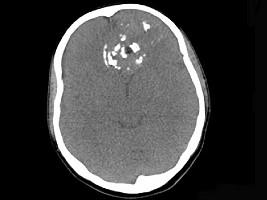

问题 男性,28岁,因鼻塞、头痛1年余,鼻窦CT扫描如图所示,请选择正确的描述与结论 ( )

选项 A、考虑鼻窦骨瘤 B、考虑为鼻窦软骨瘤 C、肿块内密度不均,有较多致密钙化影 D、窦壁及颅底骨质破坏 E、双侧上颌窦、筛窦、鼻腔及蝶窦内见软组织肿块影

答案 BCDE